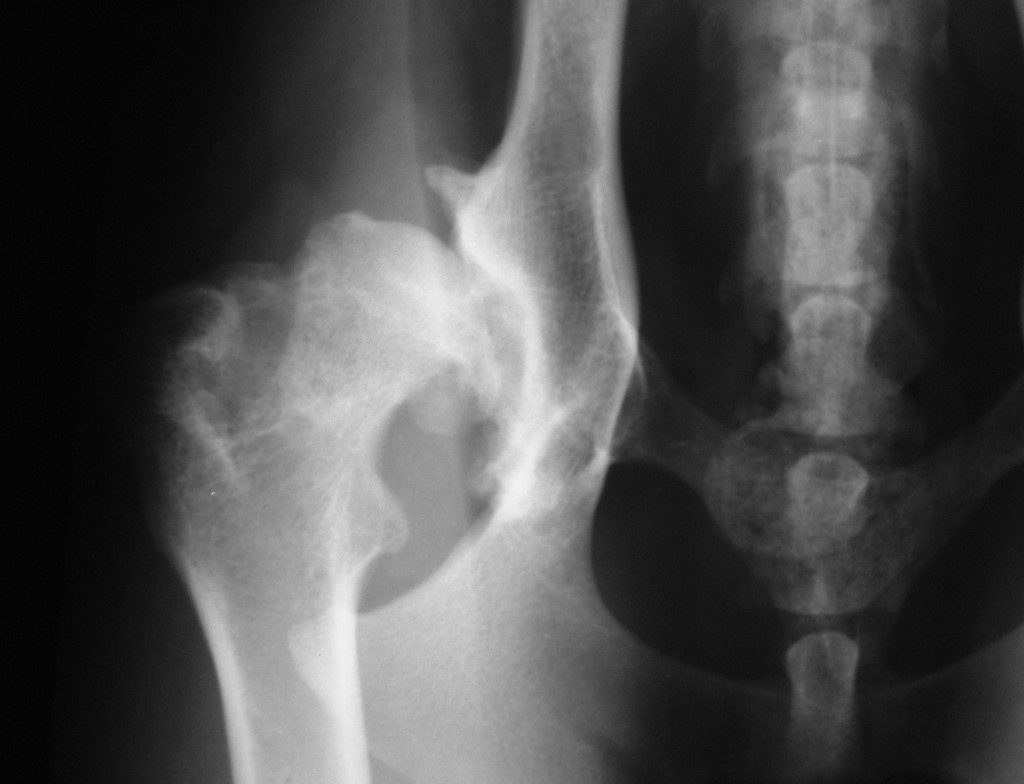

Hip Dysplasia In Older Dogs Treatment . total hip replacement (thr), the third surgical option, can be used in young dogs who cannot be successfully treated with jps or dpo/tpo. — hip dysplasia in dogs is a developmental disorder caused by a loose hip joint, which can be painful for your dog. They will conduct a thorough physical exam, assess. Discover the causes, symptoms, and treatment options for hip. Here’s how to treat and even hopefully prevent the chronic condition, according to a veterinarian. — canine hip dysplasia is a condition where the hip joint develops abnormally. For mild hip dysplasia, treatment involves: The best treatment for hip dysplasia in dogs depends on the severity of the condition and the individual dog’s needs. — what is the best hip dysplasia treatment? — diagnosis & treatment. If you suspect your dog has hip dysplasia, consult your veterinarian. Supplements that support joint health.